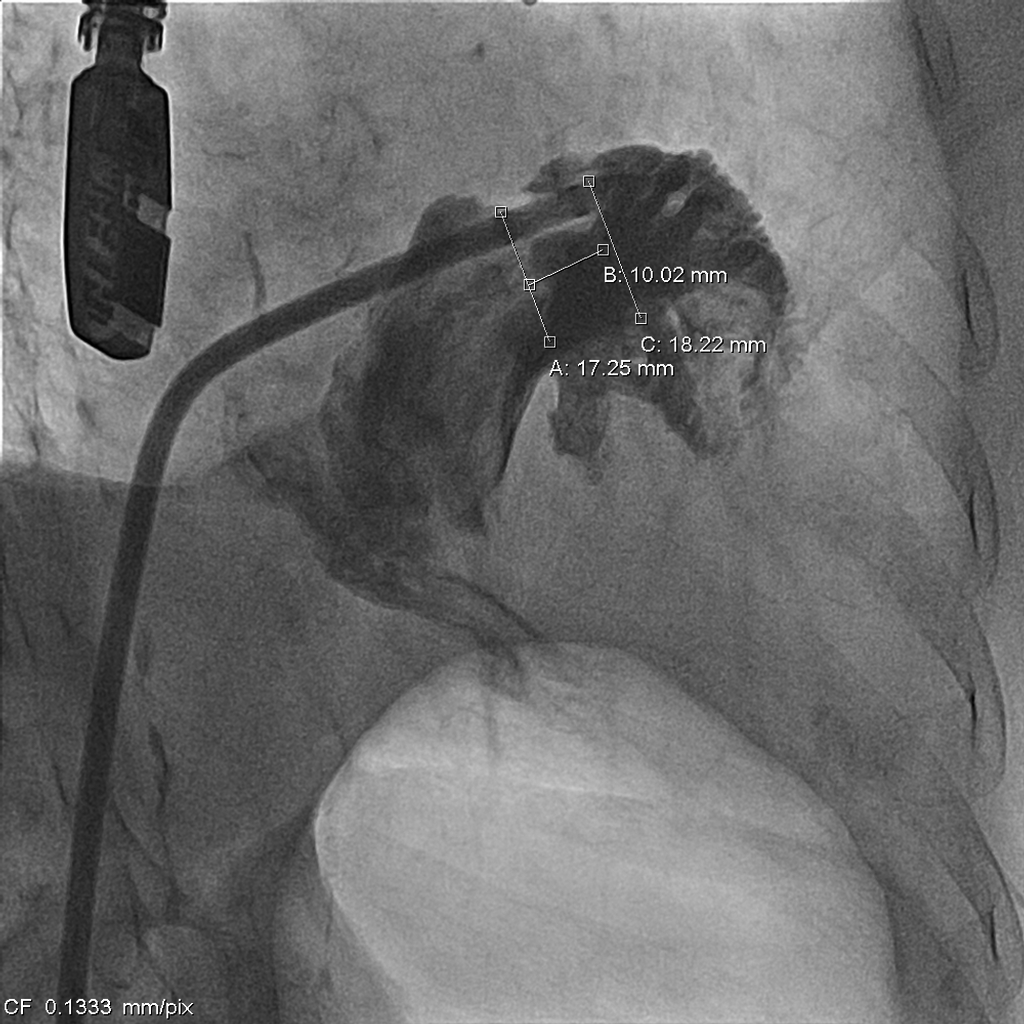

Coronary artery angiography showed only mild atheroscleorosis of left and right coronary arteriesWe used periprocedure transesophageal echocardiography to measure the size of left atrial appendage and we are going to place Lambree LAA closure systemTransseptal puncture was performed smoothly. LAA angio revealed ostial diameter was 17.3-25.3mm (diastole, systole). Landing zone diameter was 18.2-20.7mm.

1. We made right femoral vein puncture and inserted 8 Fr sheath. Then we advanced the SL0 catheter to atrial septum.2. We used BRK transeptal needle to perform transeptal puncture under TEE guidance and advanced the dilator and SL0 catheter.3. The LAAO size was chosen under TEE and under angiography and we selected the 20/26 mm Lambre LAA Closure System (Lifetech Scientific).4. We deployed the LAA occlude. But the position of the LAAO changed soonly and unstable after the deployment under angiography and TEE view. (Image 1) (Video 1) 5. The procedure was going to be closed. However, the LAAO disappeared under the TEE view and dislodged to the aortic arch at the next moment. 6. SJM 12 Fr sheath (Abbott) was inserted through right femoral artery and we chose a JR4 8 Fr. guiding catheter. We used the JR4 to crush the LAAO at first.7. Then we used the AndraSnare (Andramed) to catch the device and pulled it to the opening of the right femoral sheath.8. It was stuck at the orifice of the sheath and kinked so that we changed to larger bore Gore sheath 24F.(Image 2)9. We used Conger GW 0.035 260cm to pass through the LAAO. And then ev3 Goose Snare 10mm 4.5Fr. (Medtronic) was used to grab the wire and LAAO together. We finally made extraction of the LAAO. (Video 2)(Image3)10. The final right common femoral artery angiography showed no contrast medium extravasation.11. The second LAAO was deployed successfully by using the Watchman Pro 27mm system (Boston Scientific).(Video 3)